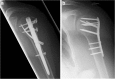

Locking nail versus locking plate for proximal humeral fracture fixation in an elderly population: a prospective randomised controlled trial

Background: Proximal humeral fractures (PHFs) are the third most common fracture in older patients. The purpose of the study was to prospectively evaluate the outcomes of PHF fixation with a locking blade nail (LBN) or locking plate (PHILOS) osteosynthesis in a homogeneous elderly patient population.

Methods: Inclusion criteria were an age > 60 years and the capacity to give informed consent. Patients with isolated tuberosity fractures, previous trauma or surgery, advanced osteoarthritis, fracture dislocation, pathological fractures, open fractures, neurological disorders, full-thickness rotator cuff tears, fracture line at the nail entry point or severely reduced bone quality intra-operatively were excluded. Eighty one patients with PHFs were randomised to treatment using LBN or PHILOS. Outcome measures comprised Constant score, age and gender adjusted Constant score, DASH score, VAS for pain, subjective overall condition of the shoulder (1-6) and active shoulder range-of-motion in flexion and abduction. Plain radiographs were obtained in two planes. All data were collected by an independent observer at 3, 6 and 12 months postoperatively.

Results: Thirteen patients were excluded intra-operatively due to rotator cuff tears, fracture morphology or poor bone-quality. Of the remaining 68 patients, 27 in the LBN and 28 in the PHILOS group completed the full follow-up. Mean age at surgery was 75.6 years and the majority of PHFs were three-part fractures (49 patients). Baseline demographics between groups were comparable. All outcome measures improved between assessments (p < 0.001). The LBN group showed improved DASH scores as compared to PHILOS at 12 months (p = 0.042) with fewer incidences of secondary loss of reduction and screw cut-out (p = 0.039). A total of 29 complications (in 23 patients) were recorded, 13 complications (in 12 patients) in the LBN group and 16 complications (in 11 patients) in the PHILOS group (p = 0.941). No significant inter-group difference was observed for any other outcome measures, nor was fracture morphology seen to be associated with clinical outcome or complication rate.

Conclusions: At short-term follow-up, LBN osteosynthesis yielded similar outcomes and complication rates to PHILOS plate fracture fixation in an elderly patient population, though with a significantly lower rate of secondary loss of reduction and screw cut-out.